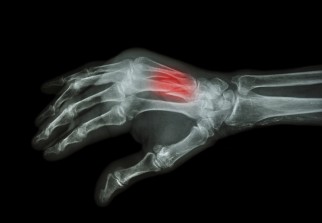

L'hormone du sommeil, la mélatonine, permettrait de lutter contre l'ostéoporose, selon une nouvelle étude scientifique ispano-canadienne.

Mais elle freinerait peut-être également l'activité des ostéoclastes, des cellules osseuses nocturnes qui encouragent le processus de dégénération des os. C'est ce que constate une étude menée sur des rats et publiée dans la revue spécialisée Rejuvenation Research.

Les chercheurs des Université de McGill au Canada et de Madrid en Espagne ont réalisé des expériences scientifiques sur des rats âgés de 22 mois (l'équivalent de 60 ans chez un être humain). Les scientifiques leur ont injecté des suppléments de mélatonine, dilués dans de l'eau, pendant 10 semaines (soit six années pour l'homme) et ont gardé un groupe témoin.

«Avec l'âge, nous dormons moins bien et les ostéoclastes (les cellules assurant la destruction du tissu osseux) sont plus actifs. Ce phénomène tend à accélérer le processus de résorption osseuse », a expliqué le professeur Faleh Tamimi, de la Faculté de médecine dentaire de l'Université McGill.

Ils ont ensuite comparé la taille et la densité osseuse des fémurs de rongeurs. Ceux qui avaient reçu un supplément de mélatonine avaient des os plus flexibles, moins fragiles et plus denses que les autres rats. « La mélatonine semble être efficace pour renforcer les os et limiter les risques d'ostéoporose » explique le professeur Faleh Tamimi.

«Si les résultats de ces premières recherches sont encourageants, des tests cliniques sur des humains doivent être réalisés, avant qu'on puisse émettre des recommandations sur la consommation de mélatonine dans le traitement de l'ostéoporose » conclut-il.